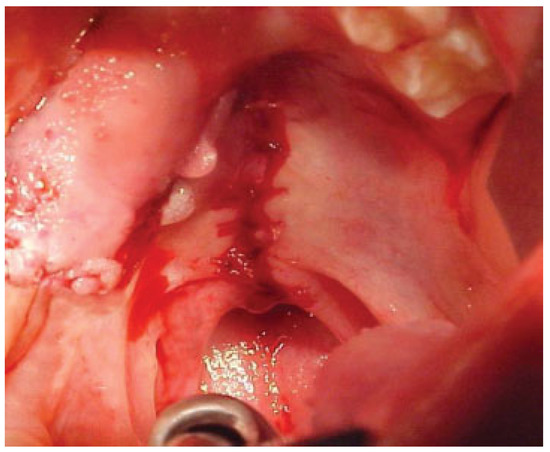

Case 9

A 7-year-old boy with a history of bilateral cleft lip and palate presented with an anterior fistula measuring 40 × 28 mm after palatal surgery (Figure 11). The fistula was closed with a left anteriorly based NAMMC flap (Figure 12, Figure 13 and Figure 14).

Figure 11. Severe fistula located on the hard palate after primary palatoplasty in an 8-year-old patient with isolated cleft palate.

Figure 12. Postoperative (1 month) view of the patient in Figure 11 after closure of the fistula using a posteriorly based nasal artery musculomucosal cutaneous flap.

Figure 13. Postoperative view of the patient in Figure 11 and Figure 12 1 year after surgery when the patient returned for soft palate repair.